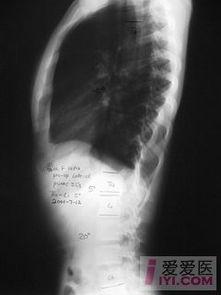

说起脊柱凹凸图,不得不提的就是欧美健身圈。在这些健身达人的世界里,脊柱凹凸图几乎成了衡量身材的标准之一。那么,什么是脊柱凹凸图呢?简单来说,就是通过特定的动作,让脊柱呈现出明显的凹凸感,从而展现出完美的身材线条。

那么,脊柱凹凸图到底有什么好处呢?首先,它可以帮助你更好地了解自己的脊柱状况。通过观察脊柱的凹凸程度,你可以判断自己的脊柱是否健康,是否存在弯曲等问题。